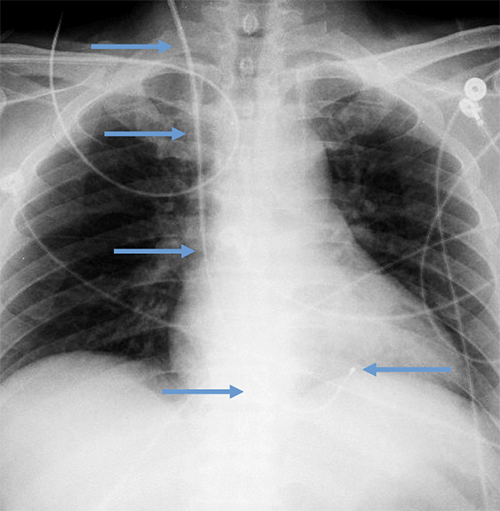

- CEID images with lead types:

Abandoned leads

Abanded leads plus generator